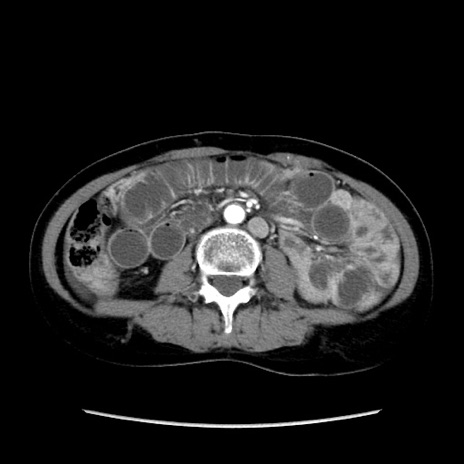

症例32(横断像)

【症例】40歳代 女性

【主訴】上腹部痛、嘔気・嘔吐

【現病歴】約9時間前頃から急に上腹部痛、嘔気、嘔吐が出現。改善しないため救急要請。

【既往歴】子宮頚癌(広汎子宮全摘術、放射線療法)、腸閉塞

【身体所見】腹部:平坦、軟、腸雑音亢進、上腹部を中心に腹部全体に圧痛あり。

【データ】WBC 8400、CRP 0.03